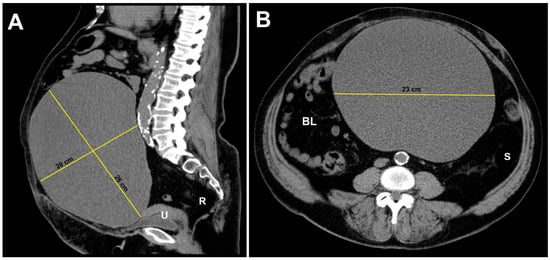

A Large Ovarian Endometrioma Occupying the Abdominal Cavity in a Postmenopausal Patient: A Case Report

2. Case Presentation